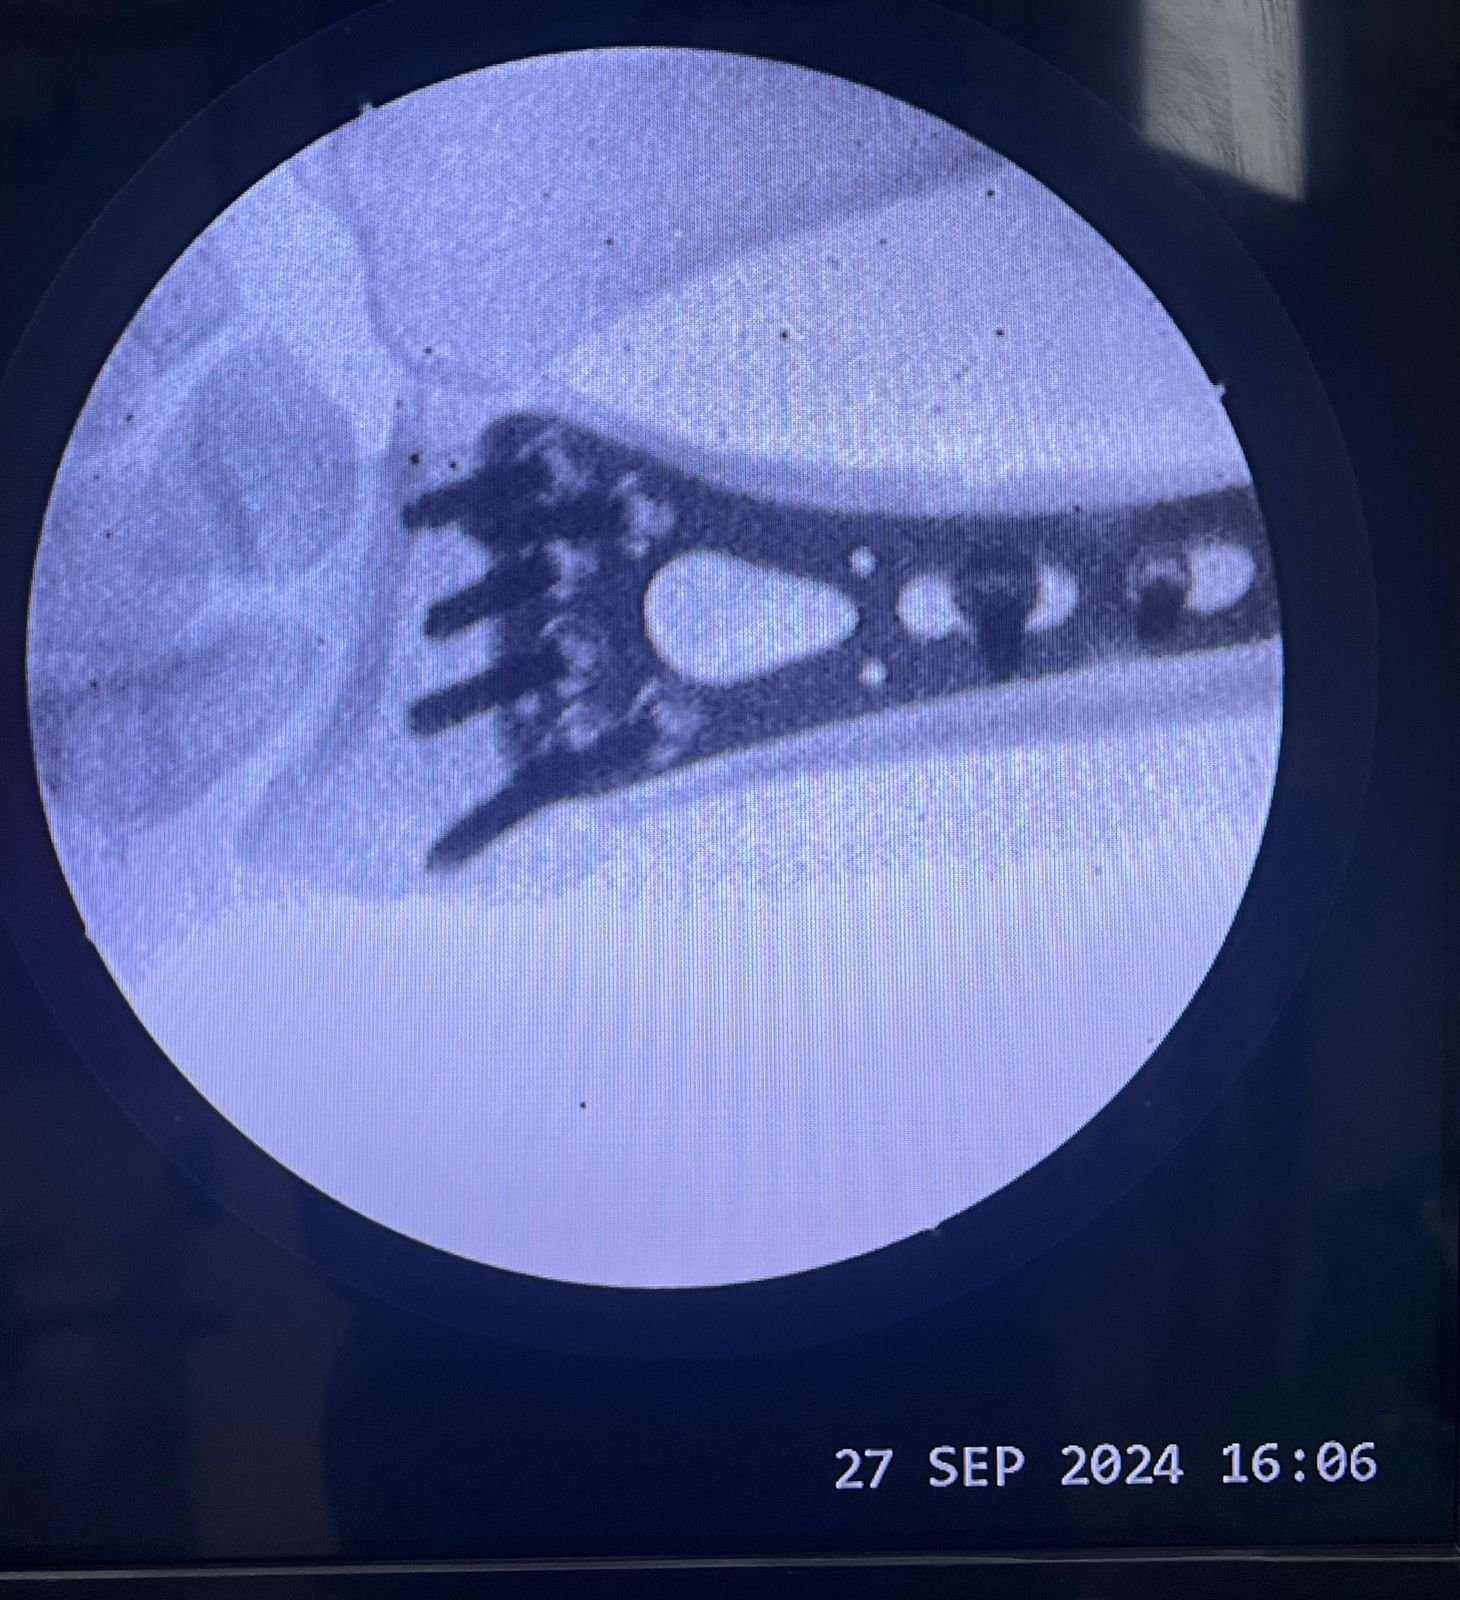

Clinic Exterior & Reception | Elbow dislocation &

operative treatment